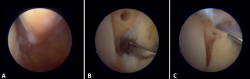

Anatomía artroscópica del complejo medial

Mediante la artroscopia podremos ver las fibras profundas del ligamento deltoideo, que es la porción intraarticular del ligamento. Medial y proximalmente a la punta del maléolo ya tenemos la inserción de la capa profunda del ligamento deltoideo. Si no hay lesión, veremos la porción anterior de las fibras tibioastragalinas profundas. Cuando existe una lesión de estas, podemos visualizar la porción intermedia y posterior. Las bandas superficiales, por su ubicación más externa, no son visibles mediante artroscopia, a no ser que no exista una lesión de las profundas (Figura 5).

Figura 5. A: visión anterior del receso medial del tobillo; B: con el palpador tensamos las fibras del ligamento tibiotalar profundo.